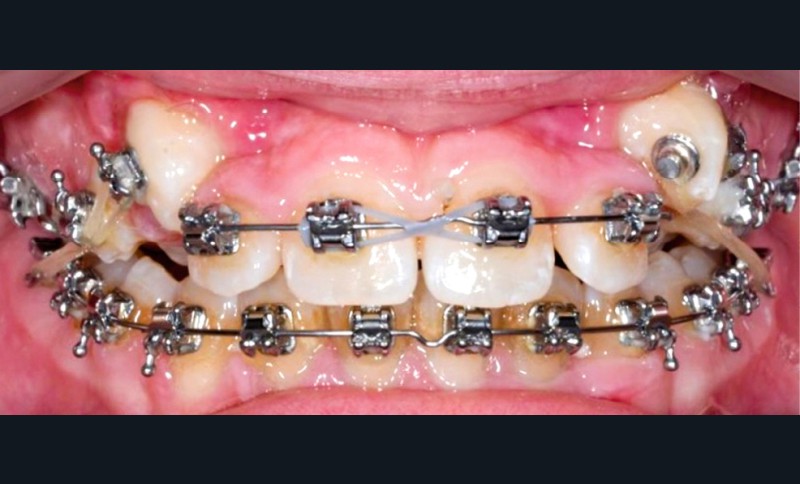

Un appareil multi-attache est mis en place avec une prescription MBT en .022 x .028. une fois les faces vestibulaires des canines maxillaires apparentes. 13 et 23 ne sont pas prises en charge dans l’arc pour éviter les effets parasites sur les dents adjacentes. Leur traction est poursuivie avec des élastiques de Classe II (1/4” – 3.5 oz) en port nocturne. Ces élastiques sont portés sur un bouton palatin pour la 23 afin de corriger sa rotation mésio-vestibulaire. Une fois les canines suffisamment proches du plan occlusal, elles sont prises en charge dans un arc continu en suivant les séquences suivantes : .014, .018 et .019 x .025 Niti. Une fois l’arc .019 x .025 en Niti en place pendant huit semaines, l’arc transpalatin est déposé. L’arcade mandibulaire suit cette même séquence d’arcs avec l’ajout d’un arc en acier .019 x .025 avec courbe de Spee inversée pour aider à la correction de la supraclusion.